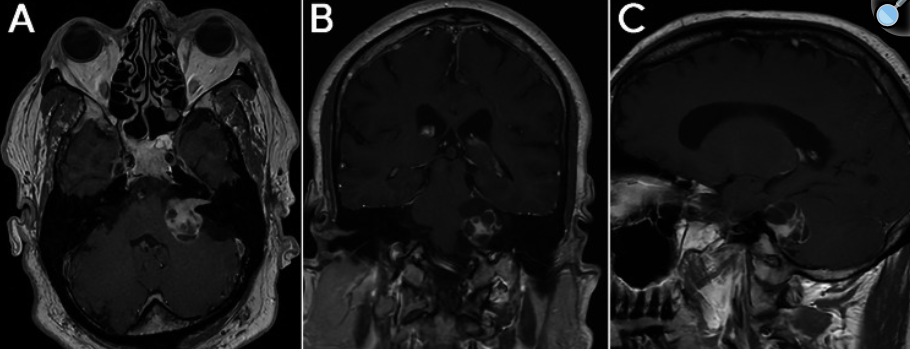

一名72岁男性于2004年首次就诊,症状表现为严重头痛、癫痫发作和步态不稳。影像学检查显示松果体区占位性病变伴脑积水。内镜下第三脑室造瘘术并行肿瘤活检,但结果未能明确诊断。患者接受了为期3年的临床和影像学随访,后失访。在随访期间,病变无明显症状,且重复MRI检查显示其大小增长甚微。 初次治疗11年后,患者因出现为期3个月的显著步态缓慢、不稳及间歇性视力模糊再次就诊。其记忆力、注意力及专注力亦进行性